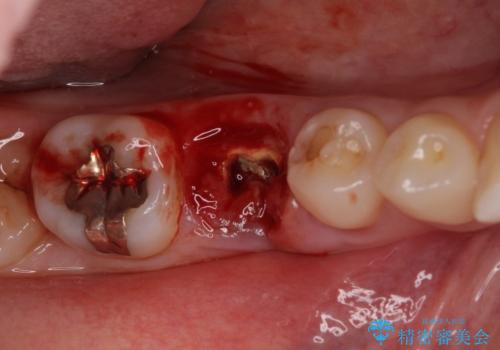

診察の結果、歯が破折しており抜歯が必要でした。

抜歯後にはストローマンSLActiveを埋入し、補綴治療を行うこととしました。